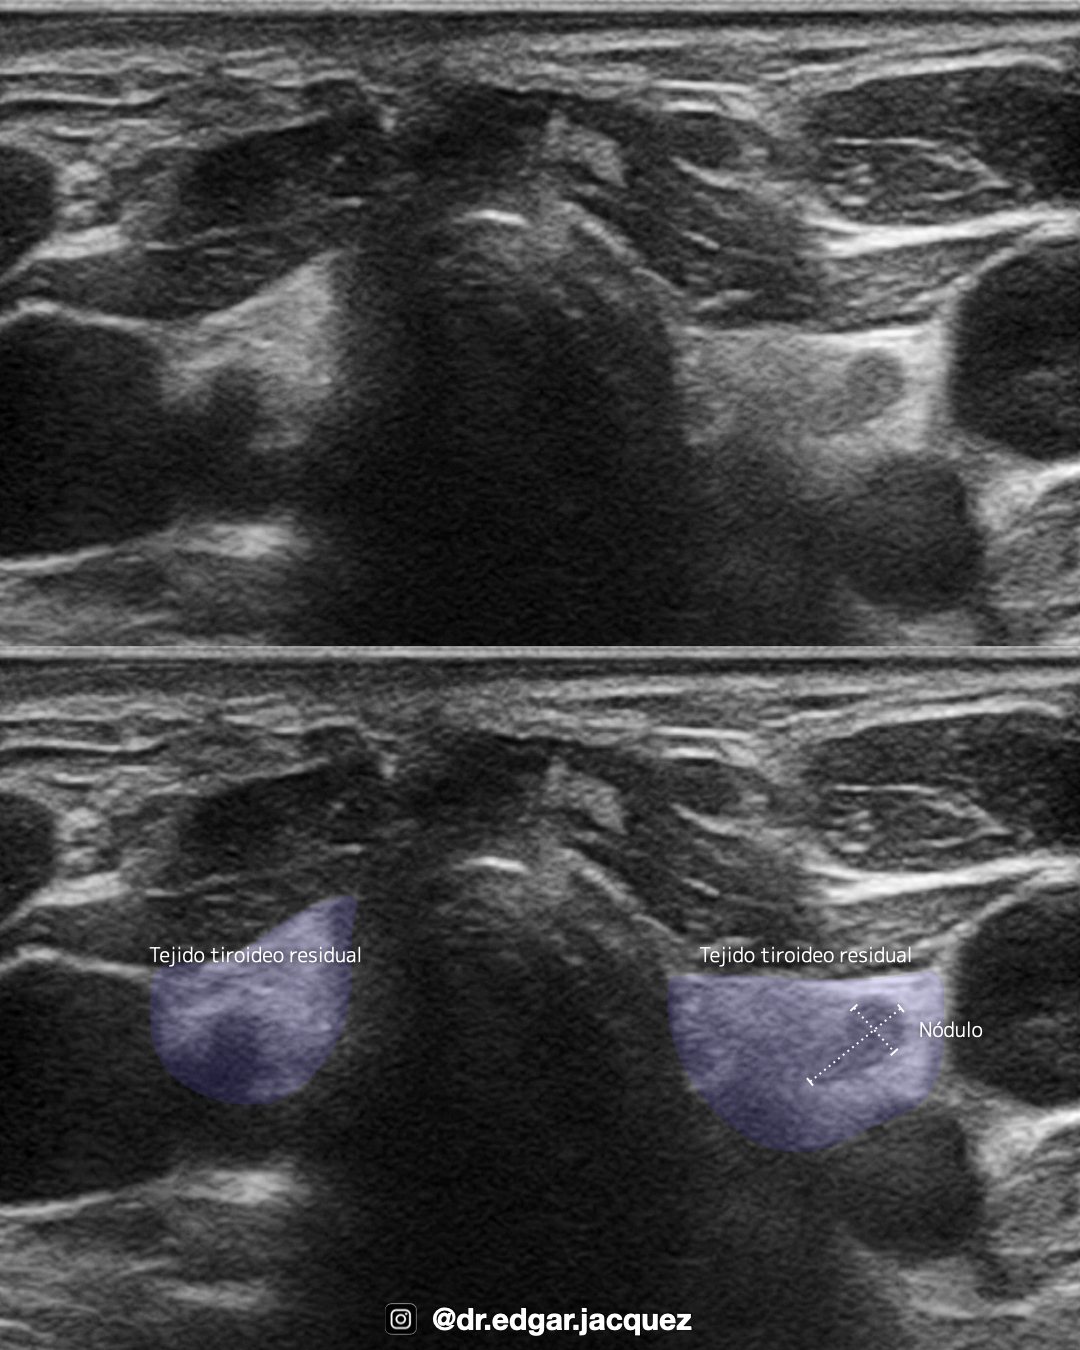

Contexto Postquirúrgico o Tiroides Atrófica

+En glándulas post-quirúrgicas o atróficas, la anatomía se encuentra distorsionada. El sistema TI-RADS solo debe aplicarse si se identifica tejido residual inequívoco que contenga un nódulo bien definido. En estos escenarios, el enfoque debe orientarse hacia la diferenciación de tejido “Viable” versus “No viable” y recurrencia locorregional.

Tejido Post-tiroidectomía

Es vital diferenciar entre tejido cicatrizal o de granulación (típicamente estable y avascular) y la recurrencia tumoral.

Semiología: La recurrencia se manifiesta como nódulos con crecimiento progresivo, márgenes lobulados y vascularidad interna detectable por Doppler.